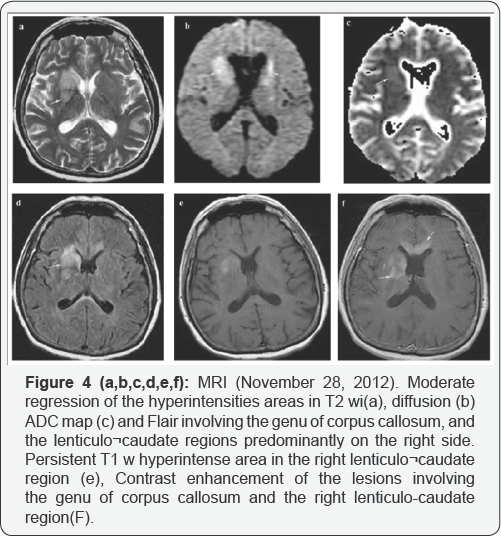

The unenhanced brain CT scan showed hypoattenuating areas involving the genu of corpum callosum and the right lenticulo-capsular region (Figure 1). Brain MRI (Figure 2) revealed multiple lesions with hyperintense signal on T2/ FLAIR sequences, isointense on T1 sequences, moderate water restriction on diffusion weighted images (DWI), some of them with moderate contrast enhancement, imprecisely delimited, localized at the level of corpus callosum, bilateral front o-insular periventricular white matter, bilateral capsulo-lenticular, right caudat nucleus, and with nodular appearance in the anterior pole of frontal lobe, left midbrain, right pons, left cerebral peduncle. The infra and supratentorial location as well as the random involvement of deep and superficial structures of gray and white matter led to the differential diagnosis among acute disseminated encephalomyelitis (ADEM), lymphoma and gliomatosis cerebri. The involvement of corpus callosum and the periventricular lesions made the diagnosis ofADEM less probable. Typical MRI findings in brain lymphomas are: homogeneous, iso- to hypointense T1 wi mass; iso- to hyperintense but often hypointense to gray matter on T2 wi with vasogenic edema; contrast enhanced T1 wi: homogeneously enhancing lesion with involvement of corpus callosum; diffusion- DWI: restricted diffusion of lesions secondary to hypercellularity, some of these MRI aspects were encountered in the presented case. The glioma hypothesis was less plausible because glioma usually shows T1-hypointense mass within white matter, with central heterogeneous signal (necrosis, intratumoural hemorrhage), variable enhancement, typically peripheral and irregular, hyperintense on T2-sequences, surrounded by vasogenic oedema and including flow voids (Figure 3). The Blood biochemistry including lactate dehydrogenase, hemoglobin, hematocrit and cell blood count were within normal range. Cerebral spinal fluid analysis showed: 7 monocytes/mm3, 0.6g/l protein (normal range =0.1-0.3g/l), 48.8mg/dl glucose (normal range 74-106mg/dl), negative bacteriological examination, negative 14-3-3 protein and absent oligoclonal bands. The bone marrow aspirate was normal, therefore a systemic lymphoma with secondary brain involvement was excluded. Enzyme- linked immunosorbent assay for detection of antibodies against human immunodeficiency virus (HIV), hepatitis B and C viruses, Epstein-Barr virus, herpes simplex virus 1 and 2, cytomegalovirus and JC virus revealed normal results. Immuno- serology showed normal immunoglobulins (IgG, IgM, IgA, IgE). After corticosteroid treatment an important clinical remission occurred, but with moderate regression of lesions on brain MRI (Figure 4 & 5). The anatomo-pathological examination of brain tissue obtained by brain stereotactic biopsy showed non Hodgkin lymphoma with large B cell. Immunohistochemical analysis revealed: lymphoma cells were positive for CD20 (diffusely distributed into the tumor) and negative for CD3, Ki67 was positive in more than 80% of tumor cells, and rare, reactive, small lymphocytes were present (Figure 3). Spinal cord MRI, contrast enhanced computed tomography of chest, abdomen and pelvis, and dilated eye examination were normal. The patient received four courses of chemotherapy combining high doses of cytarabine, methotrexate, idarubicin, dexamethasone, vincristine and ifosfamide followed by whole brain radiotherapy. The first course of chemotherapy produced an important clinical and neuroimaging remission but a new relapse occurred and the patient died 6 months later.

The typical MRI lesions of PCNSL [8] are solitary, single or multiple, homogenous, with less prominent perilesional edema, located central hemispheric, in the periventricular white matter or superficial adjacent to the meninges, with intraocular involvement in 25% of cases. On precontrast T1 weighted images, lesions are usually isointense or hypointense with strong homogenous enhancement, on T2/FLAIR appear isointense, hyperintense or hypointense, on DWI are hyperintense and on apparent diffusion coefficient (ADC) are hypointense. Lesions can disappear after corticosteroids or even spontaneously, being called "vanishing tumors". Frontal lobe location is present in 20%-43% of PCNSLs, whereas the basal ganglia are involved in 13%-20%. The corpus callosum is also frequently involved. In atypical imaging characteristics DWI, perfusion MRI and MR spectroscopy may help to differentiate CNS lymphomas from other brain lesions. DWI measures the diffusion of water molecules in biologic tissues and is considered a surrogate marker of tumor cellularity. Because PCNSL are highly cellular tumors, water diffusion is often restricted, making them appear hyperintense on DWI and hypointense on ADC maps. This characteristic is found also in: acute ischemic stroke, central necrosis of brain abscesses, the solid portion of high-grade gliomas, and some metastases. Nevertheless, PCNSL lesions have in most of cases more restricted diffusion and lower ADC values than high-grade gliomas and metastases [9]. Repeated ADC measurements may be used as biomarkers in the surveillance of therapeutic response of PCNSL [10]. Our case was particular because it showed that atypical, diffuse, imprecisely defined lesions, usually found in immunodeficient patients, especially HIV positive, can be also present in PCNSL in immunocompetent patients.